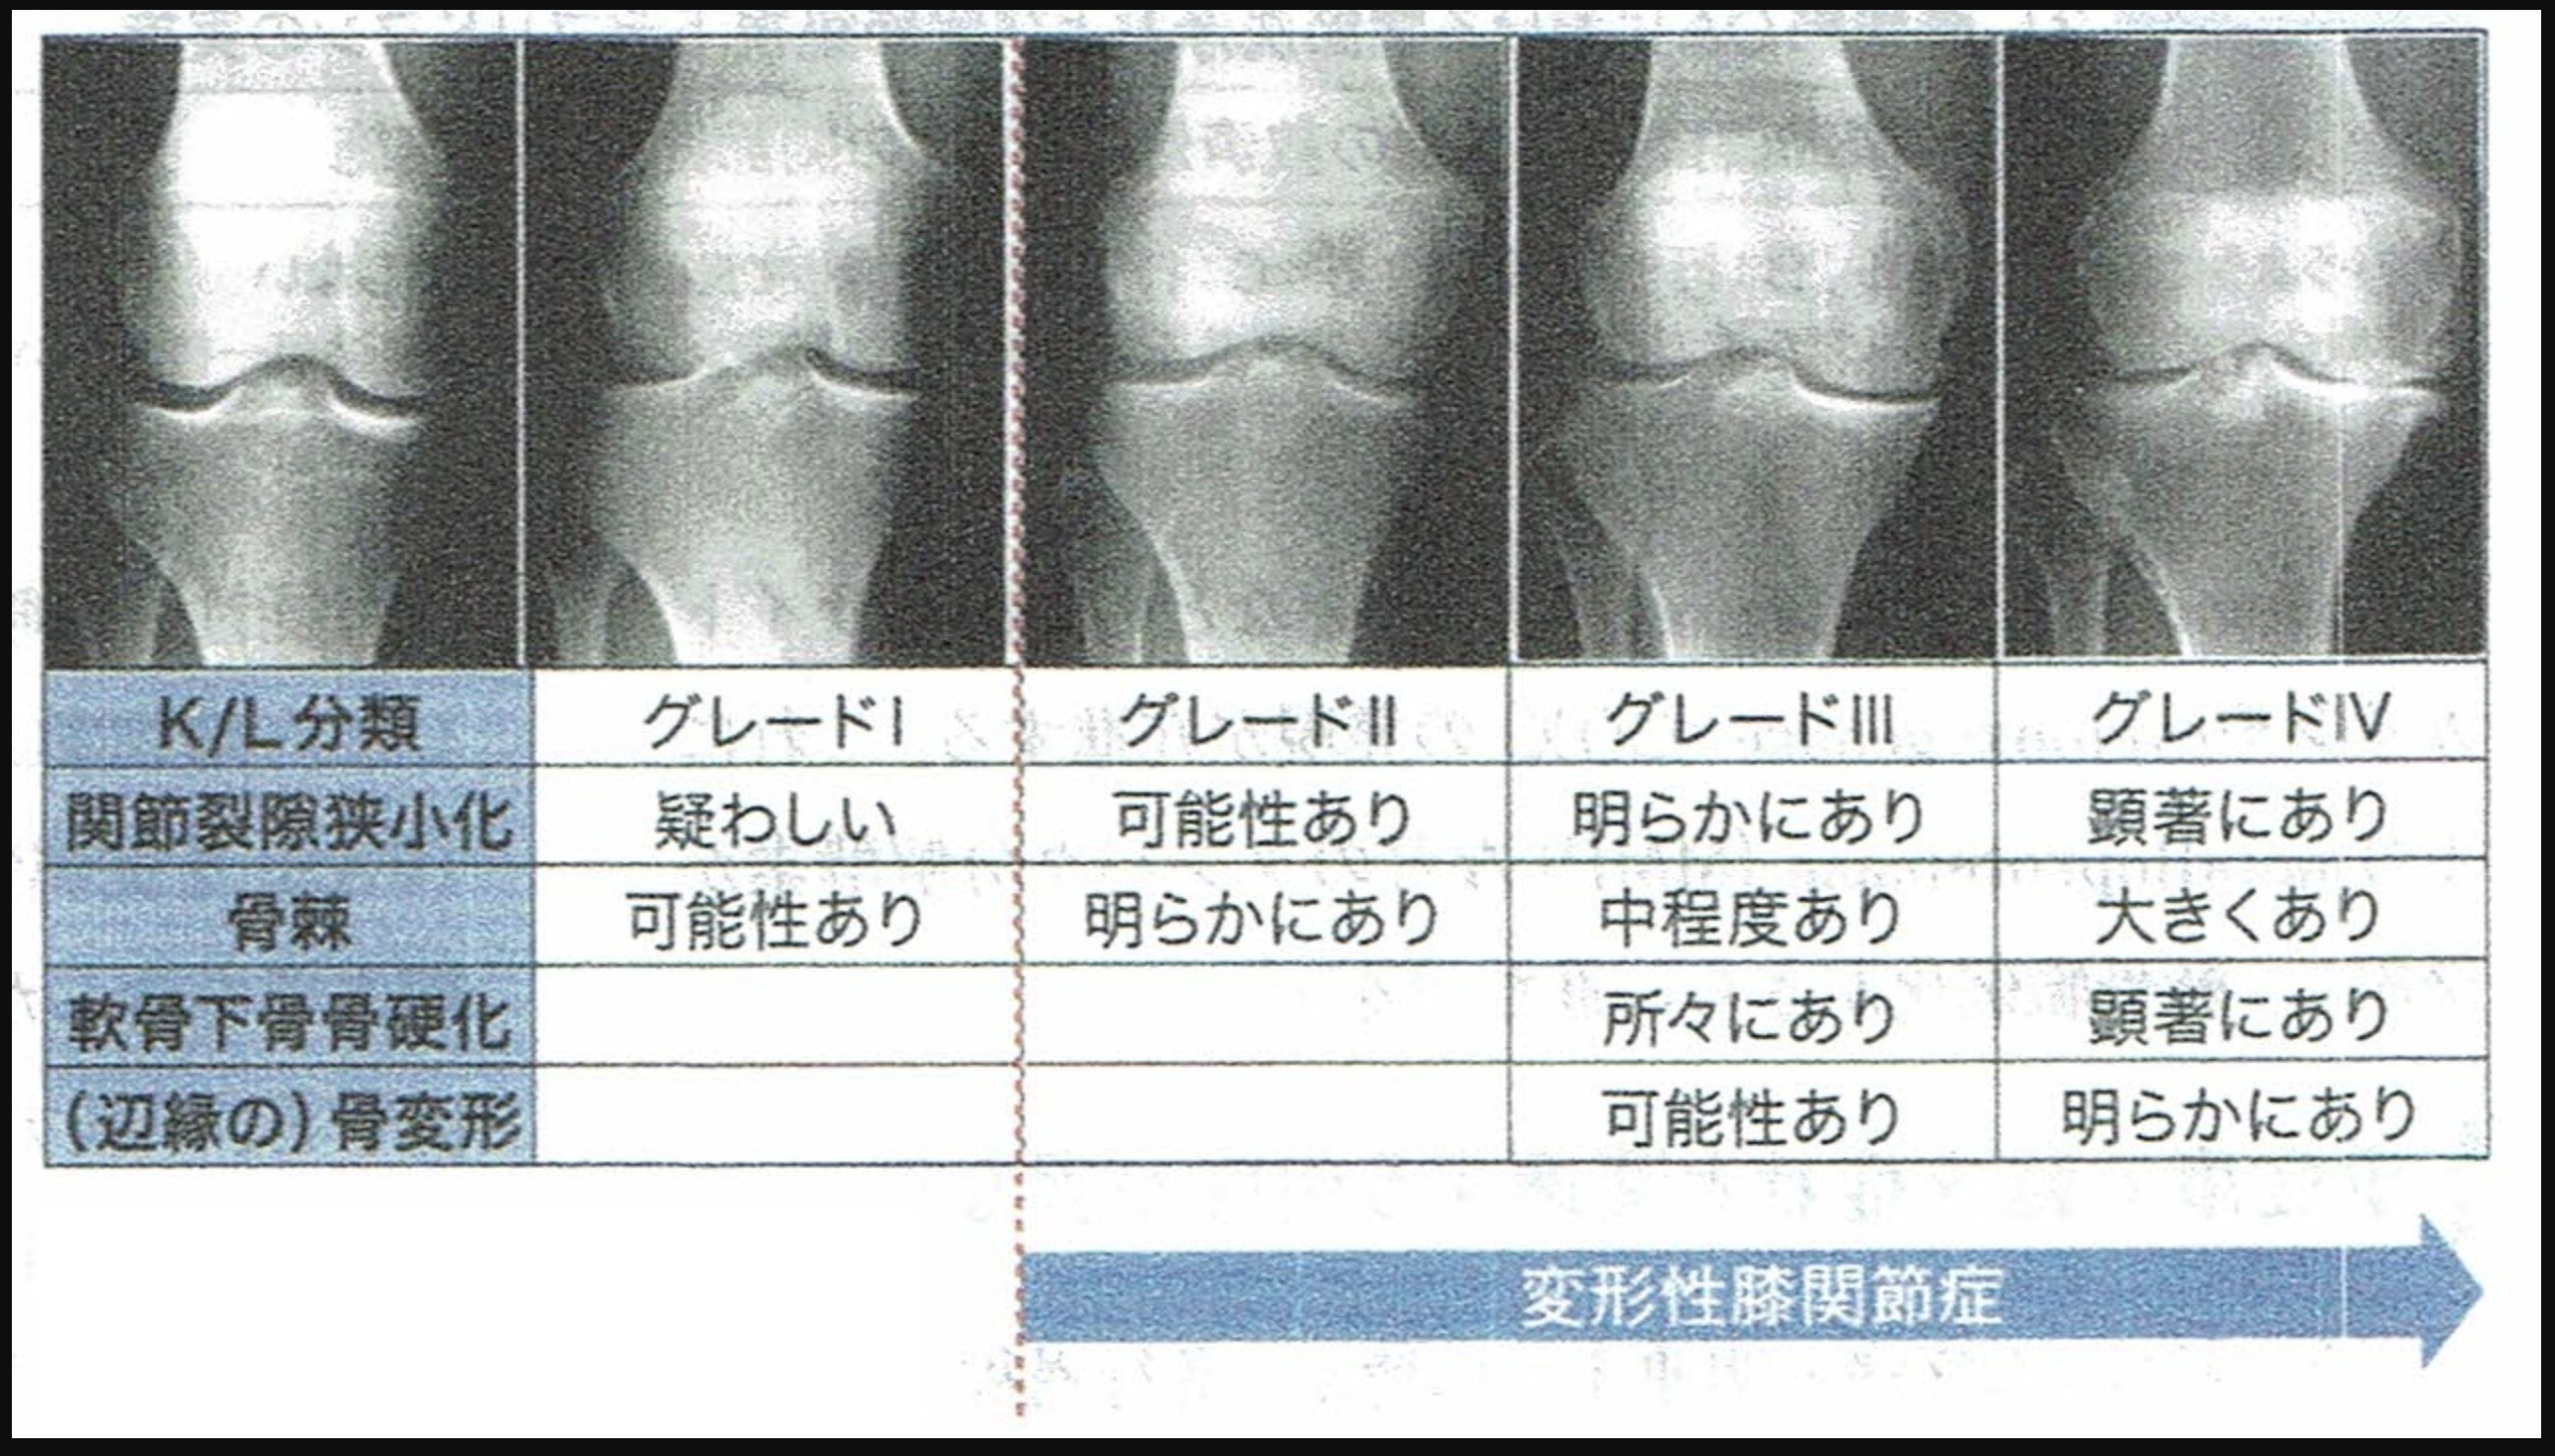

*ちなみにKL分類は下記の分類です。

3)レントゲンの分類をもとに、外表面写真を正常群22例(グレード0とグレード1)、変形性膝関節症群35例(グレード2,グレード3,グレード4)の2群に分類